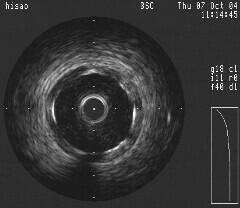

最終的にはこの症例がどうなったかというと、本当はfilter wireやocclusion balloon

を入れて血栓かどうか確認したかったのですが、術者は残りのLCXをやるのにあせって

いてできずステントをいれられてしまいました。ステント留置後のIVUSも添付します

が、こぶはなくなってました。